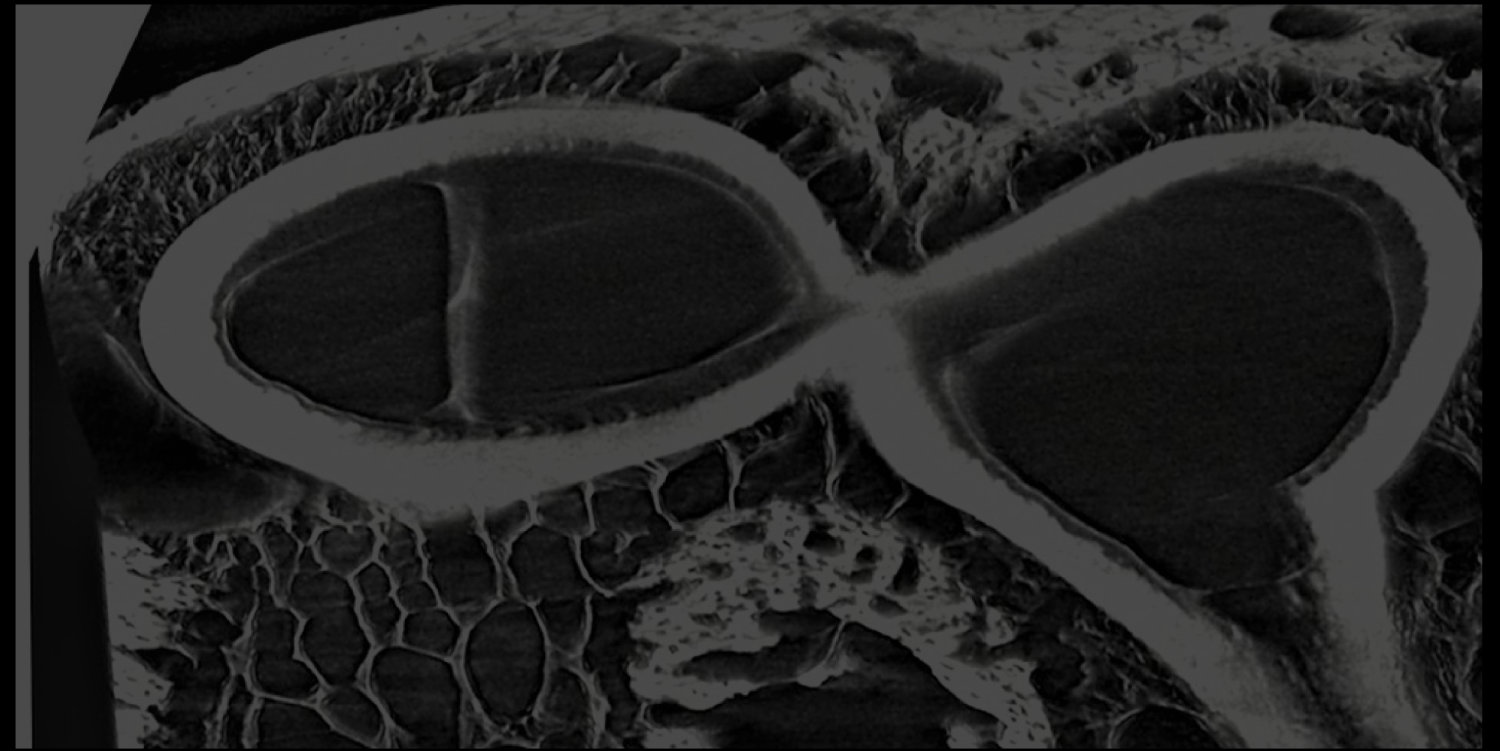

Our approach is focused on understanding the micro and mesoscale to achieve macroscale functional manipulations that can be translated to the clinical setting.

In the lab we are combining different modalities of 3D imaging, mechanical testing and tissue composition analysis, molecular biology and tissue engineering. These modalities include microCT, AFM, Light sheet, multiphoton microscopy, proteomics, Raman spectroscopy as well as computational tools for image and data analysis.